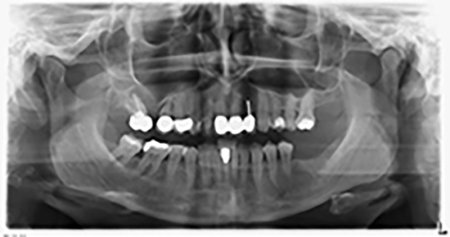

The 59-year-old patient presented with an advanced case of periodontitis, describing an unpleasant feeling and poor taste from the first quadrant in a distal direction. The clinical examination revealed generally enlarged periodontal pockets and very advanced bone atrophy in regions 16 and 14. The radiology confirmed the findings (Fig. 1). Teeth 16 and 14 could not be retained.

About six months after teeth 16 and 14 were extracted, a digital volume tomography (DVT, Planmeca) examination was performed for planning and risk minimization purposes. It clearly showed that the bone had not regenerated to the desired volume (Fig. 2 to 7).

A sinus floor elevation is required in both region 16 and region 14 to guarantee a fixed restoration based on at least two implants. Relatively large-scale bone augmentation is required due to the residual bone volume being extremely low in this case. Major bone augmentation procedures are invasive and linked to higher patient morbidity, as well as being time-consuming and expensive. It is more difficult to predict the results of the treatment and the risk of failure is increased. The patient was informed of the increased risk and was offered a removable solution, which she consistently rejected.

To restrict the augmentation to region 14, and in consultation with the patient, it was planned that implant 16 would be placed, inclined, in the dorso-cranial direction (Fig. 8).